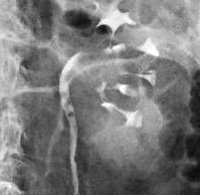

Рентгеновская диагностика (экскреторная урография и ретроградная уретерография) выявляют дефект контрастного заполнения мочеточника в месте опухоли, дилатацию мочеточника и лоханки, гидроуретеронефроз. Катетеризация мочеточника при подготовке к ретроградной уретеропиелографии сопровождается характерным симптомом Шевассю - гематурией при прохождении катетера через препятствие и прекращением выделения крови после преодоления зоны расположения опухоли. Для ретроградных уретерограмм характерны признаки затекания контраста по сторонам от дефекта в виде «змеиного языка».